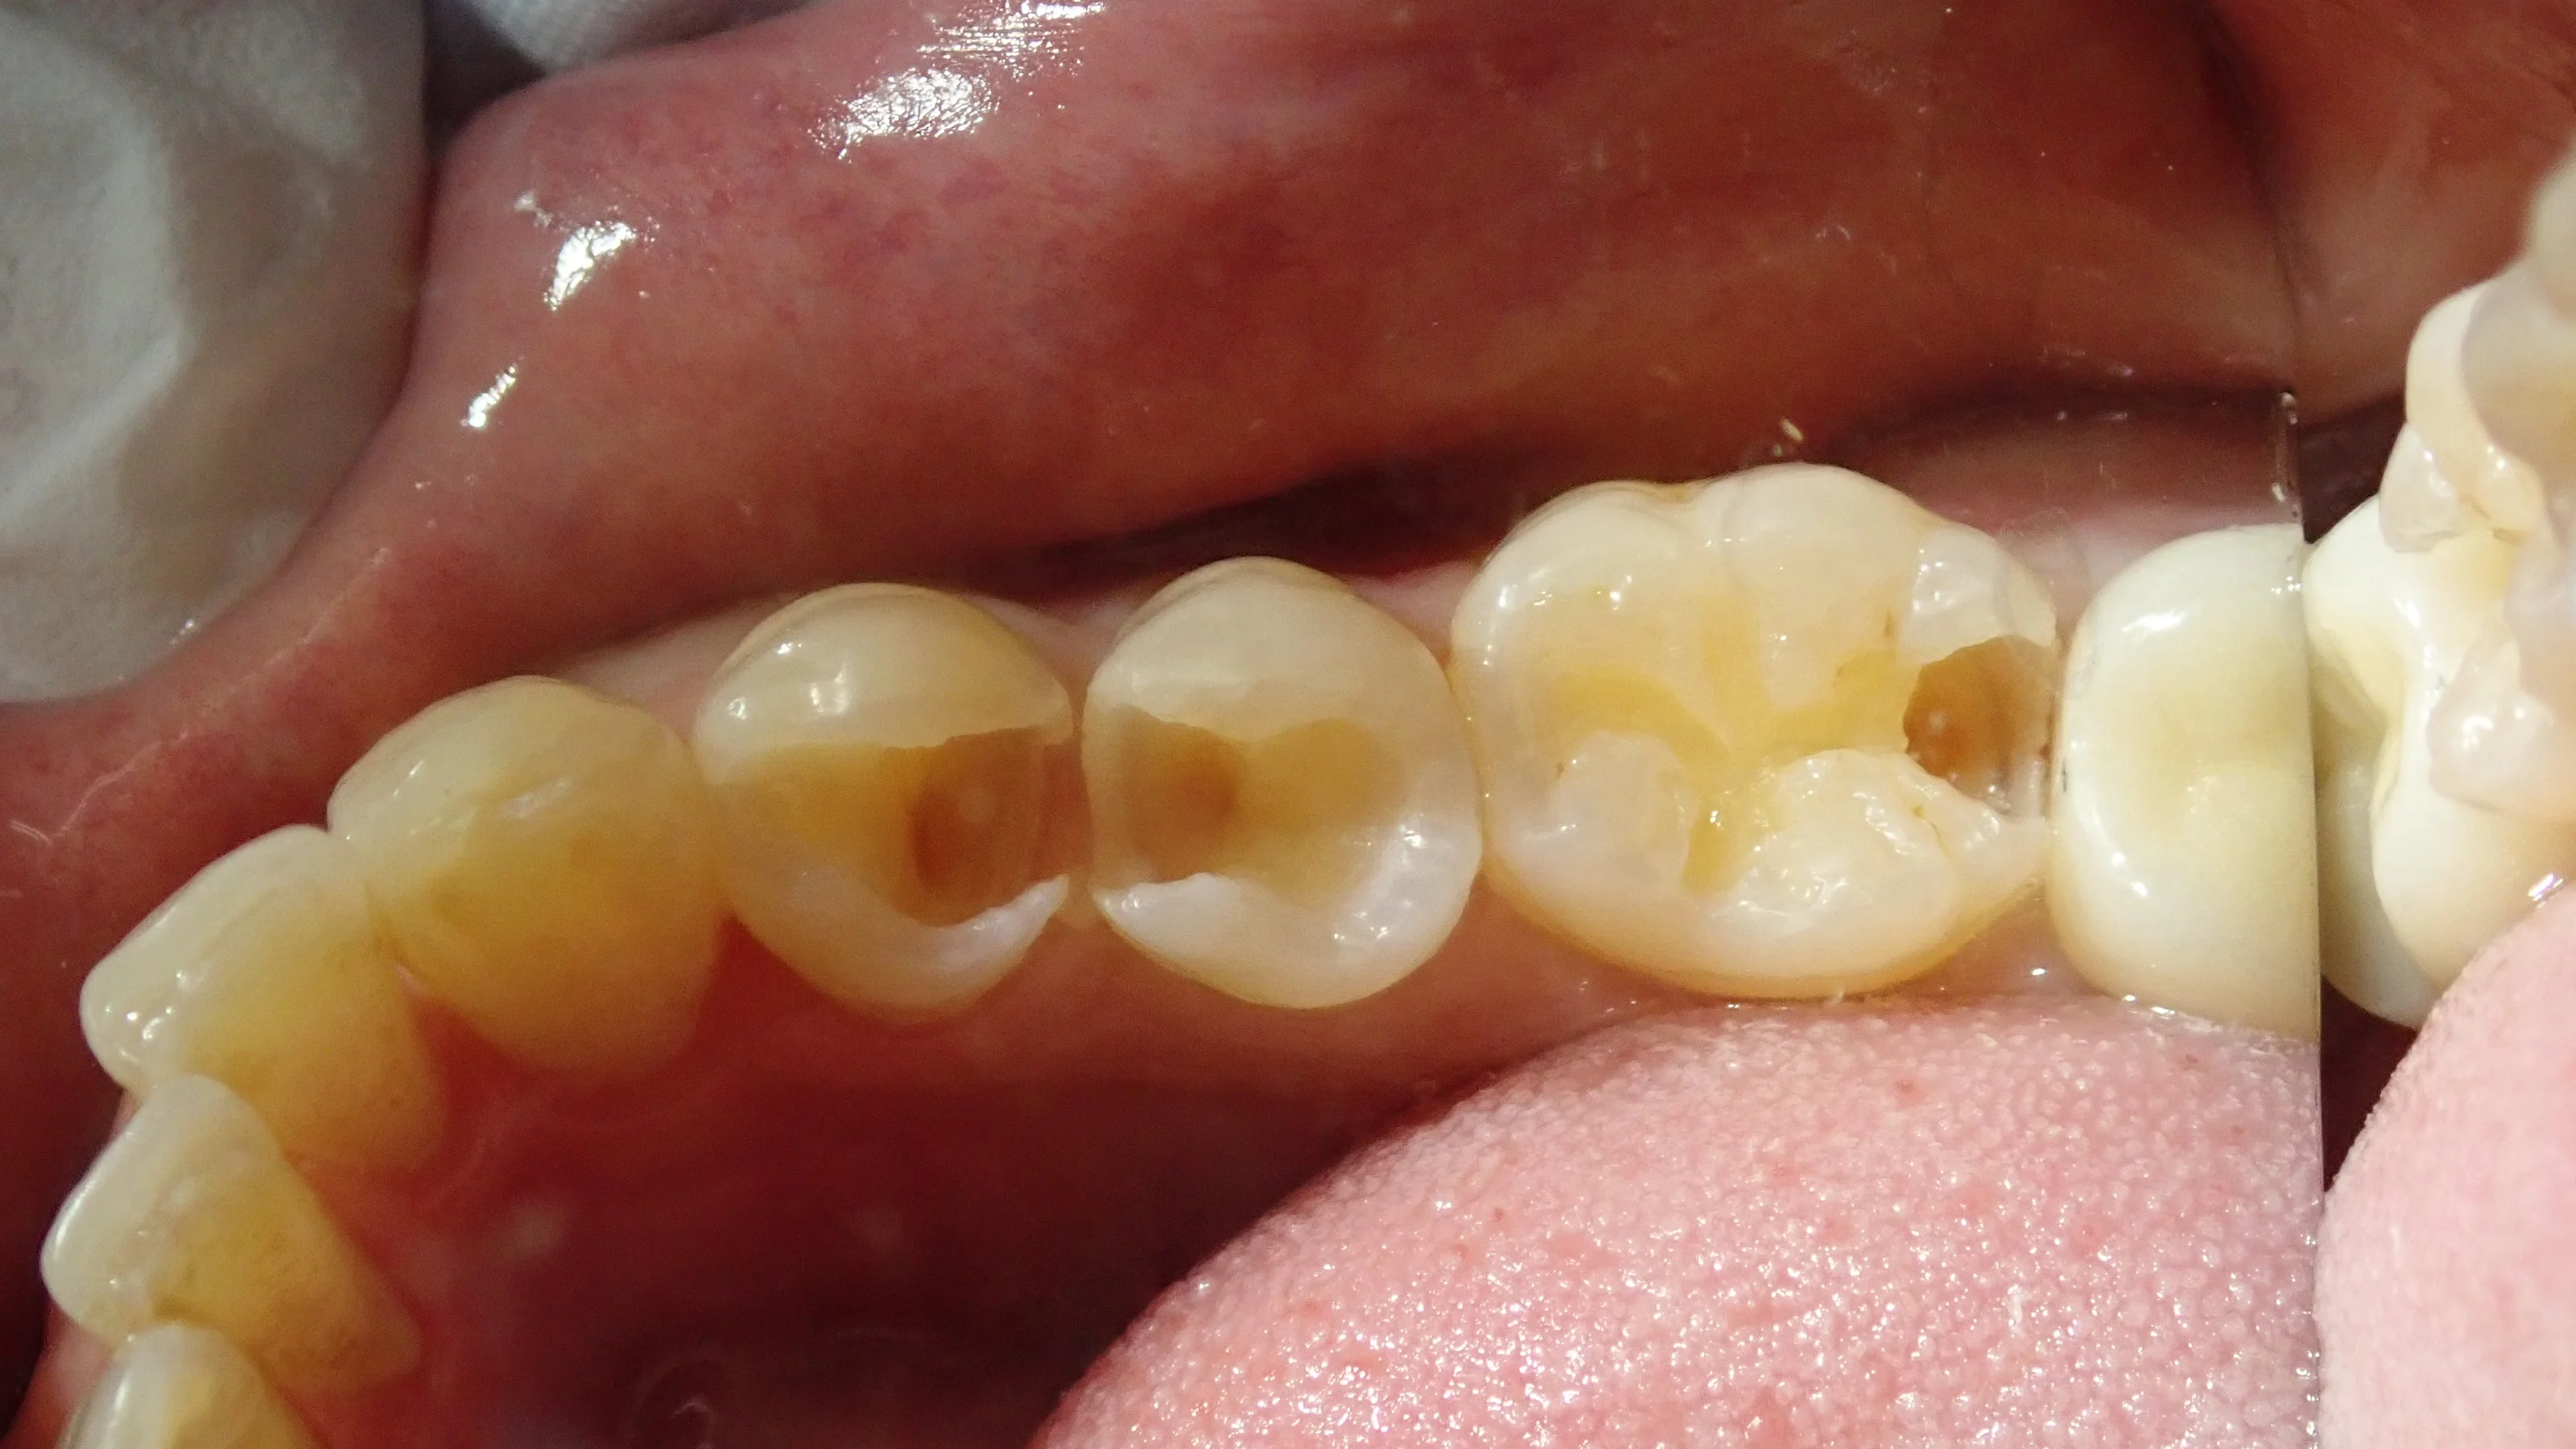

取りきったのがこちらの写真です。

手前二つは非常に大きく、神経ギリギリまで虫歯が進行していました。

着色が残っていますが、ここには色がついているだけで細菌は存在しない部分になります。

ここを取りきると神経への大きなダメージにつながるので、取ってはいけない部分でもありますね。

あまりにサイズが大きく、歯の半分はもうない状態で、表面のエナメル質という部分のみが残存している状態になります。

そのため、詰めるときの収縮(重合収縮といいます。)でエナメル質が割れないように、その収縮量をコントロールしつつ詰める必要があります。

大きな虫歯を詰めるときには、そこら辺の知識と感覚が必要になってくるので、ここら辺も歯科医師による差につながる部分でもありますね。